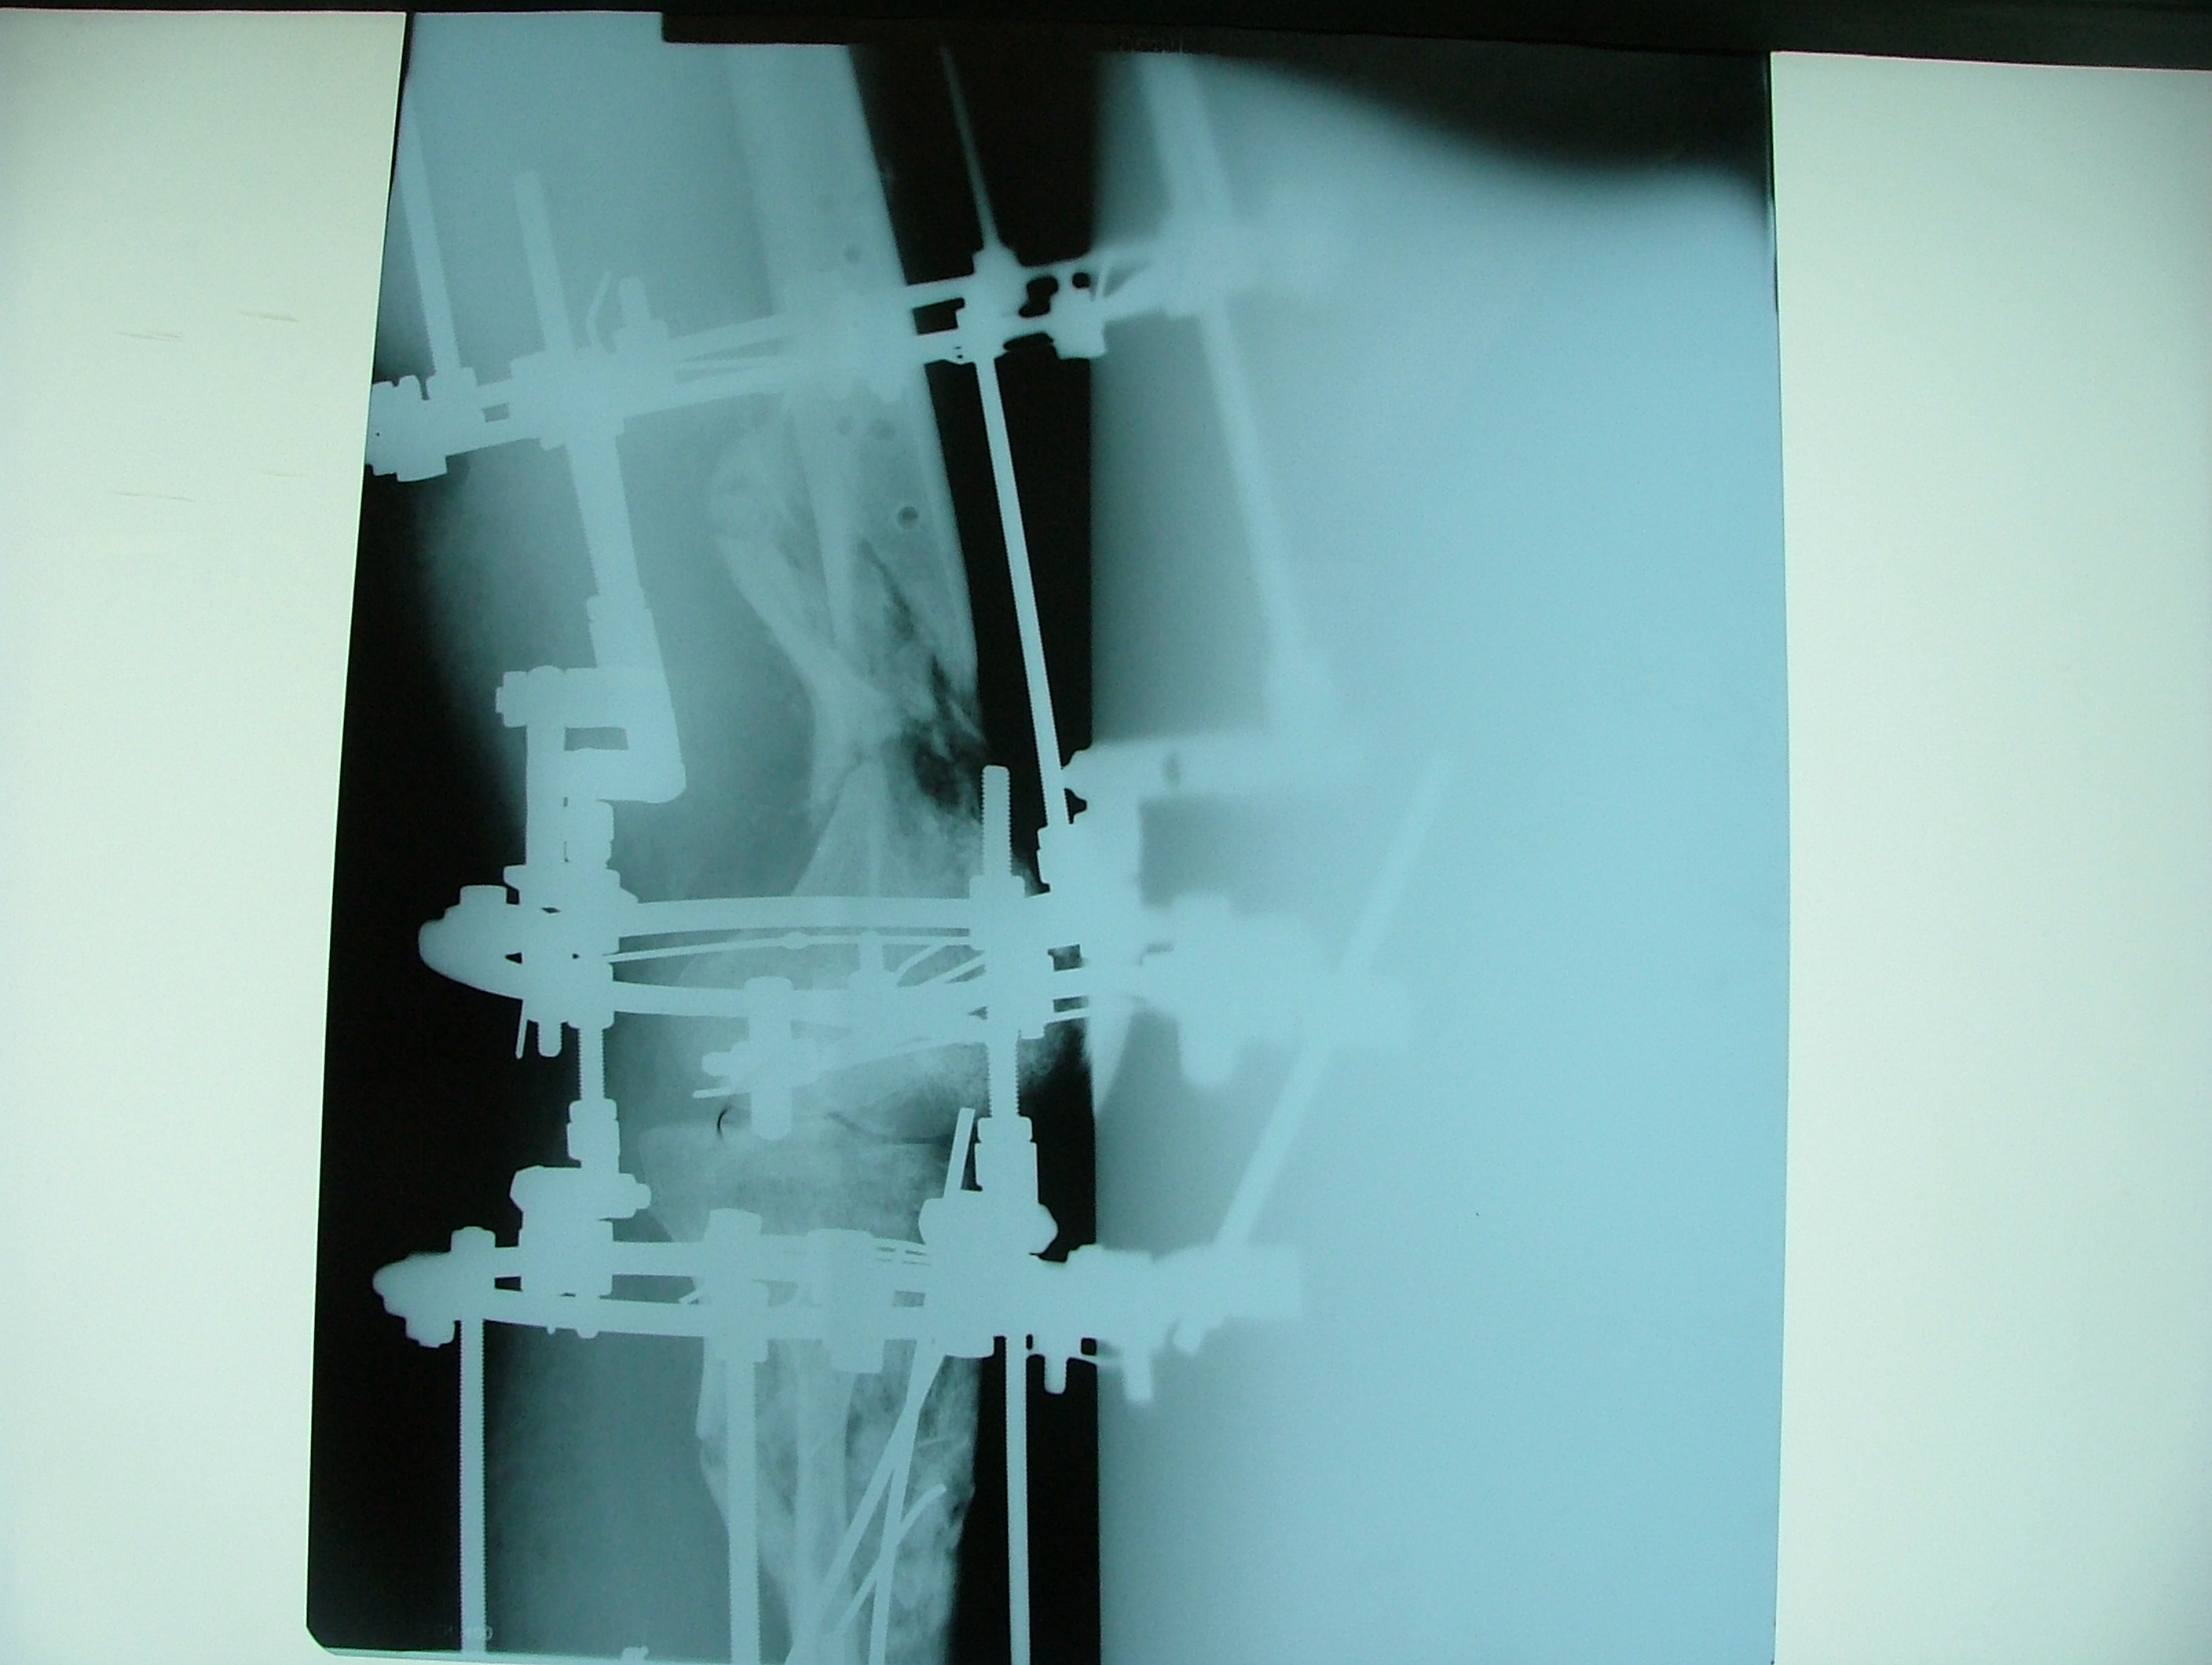

تهیه و تامین تجهیزات ارتوپدی و مشارکت در انجام اعمال جراحی ارتوپدی و عمل‌های نادر عضو تیم جراحی افزایش قد -جهت ترمیم شکستگی های قدیمی و جوش نخورده گی ها -طویل کردن اندامها- طویل کردن انگشت قطع شده - تعویض مفصل لگن _تعویض مفصل زانو _ بازسازی رباطACLوPCL_اصلاح ناهنجاریهای مادر زادی -با همکاری پزشکان و متخصصان مجرب آموزش دیده در روسیه و اتریش و سوئیس بروش جراحی ایلیزاروف و lon و lsa و واگنر و اسلایدینگ نیز جدید ترین روش افزایش قد و اندام در سال 1397 بنام hil هیل برای اولین بار- افزایش قد به 6 روش جراحی و جدیدترین روش در اروپا و روسیه. آدرس مطب _تهرانسر بلوار اصلی مجتمع سهند طبقه4 واحد 410

قطعات الیزاروف:

الیزاروف دارای عناصر اولیه و عناصر ثانویه است:

Bolt slotted-pin-ringعناصر اولی:

ها را به هم وصل می کند. .ringعناصر ثانویه: تمام قطعاتی که

پین ها باید در دو طرف رینگ گذاشته شود تا رینگ تاب نخورد،واشر کونیکال یا اسفریکال واشر تا 5/7(نیست به رینگ) درجه زاویه به راد می دهد .

باکل:وسیله ای که روی رینگ می چرخد                                            رینگ اومگا:برای بالای بازو و (یاهومروس)

rodیاpostفراموش نشود: استفاده از واشر شیار دار زیر

برای فیکس یک قطعهrodفراموش نشود  استفاده ا ز  واشر شیار  دارد در وسط

وایر ا لیزاروف  باسر بایونت(سوراخ کردن دیافیز) و تروکار(سوراخ کردن متافیز داپی فیز- سر پهن دارد)

-مقدار کشش وایر بین 130تا50 کیلوگرم است .

-  اگر نتوان دهانه تنشنر را روی رینگ گذاشت باید بین آنها یک سوکت قرار داد .

- مکعب رزوه دار برای نصب پین در زاویه های مختلف هم مفید است .

تهیه و تامین تجهیزات  ومشارکت در انجام اعمال جراحی  ارتوپدی

-جهت ترمیم شکستگی های قدیمی و جوش نخورده گی ها -

طویل کردن اندامها- طویل کردن انگشت

-اصلاح ناهنجاریهای مادر زادی

باهمکاری پزشکان و متخصصان مجرب بروش جراحی ایلیزاروف